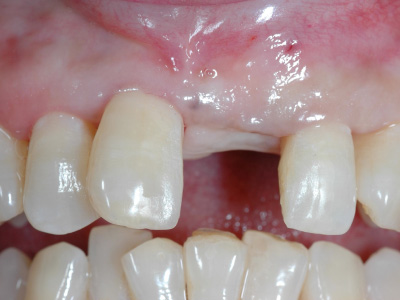

そこで、上顎から切り取ってきた歯茎をインプラント周りに移植し、歯茎に厚みを持たせます。

歯茎の移植によって歯茎の隙間が埋まり、より自然な見た目を実現できました。